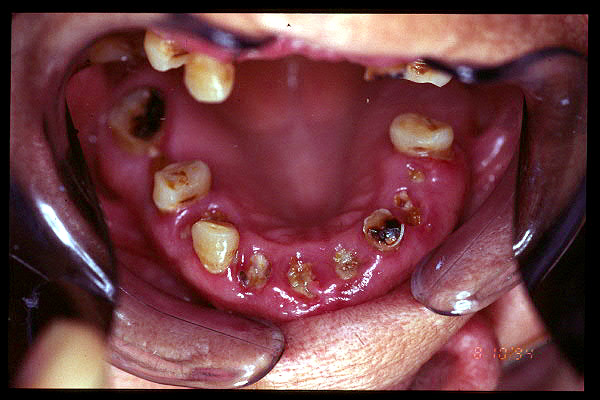

CM Edentulismo parcial, restos radiculares, caries y placa bacteriana